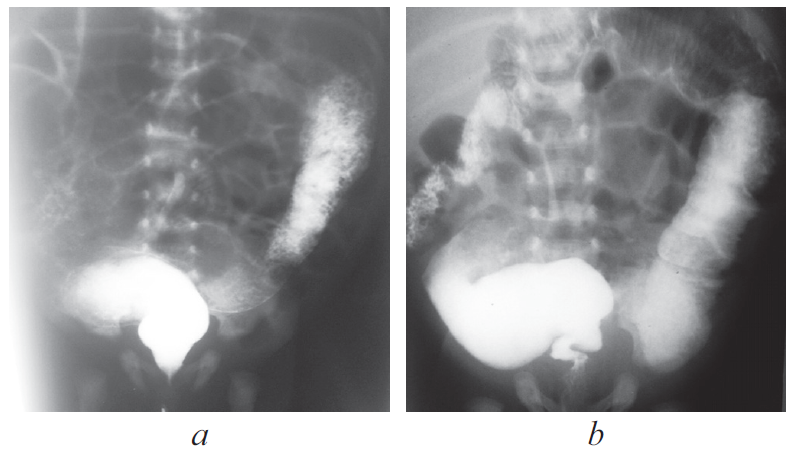

Доношенный полновесный ребенок поступил на 5-е сут жизни в стационар с жалобами на вздутие живота, срыгивания с примесью желчи и отсутствие стула. На обзорной рентгенограмме брюшной полости выявлено равномерное распределение газа по кишечнику без уровней жидкости и раздутая на всем протяжении газом толстая кишка (рис. 1, 2).

Рис. 1. Обзорная рентгенограмма брюшной полости

Fig. 1. Plain abdominal X-ray

В хирургический стационар поступил ребенок на 2-е сутки жизни с клиникой кишечной непроходимости. По данным обзорной рентгенографии и ирригографии заподозрена болезнь Гиршпрунга (рис. 5, 6).

Рис. 5. Обзорная рентгенограмма брюшной полости

Fig. 5. Plain abdominal X-ray

Рис. 6. Ирригография

Fig. 6. Contrast enema

Ирригография является обязательным исследованием у всех детей с подозрением на болезнь Гиршпрунга [2]. Чувствительность и специфичность метода по литературным данным достигает 70 и 80 % соответственно. Хорошо известно, что диагностическая значимость ирригографии в определении переходной зоны у новорожденных с болезнью Гиршпрунга меньше, чем у детей более старшего возраста (65 против 75 %) [3]. I.R. Diamond et al [4]. описали возможные предрасполагающие факторы получения ложноположительных результатов при выполнении контрастного исследования у пациентов с болезнью Гиршпрунга, одним из них является возраст ребенка. У детей в возрасте 30 сут жизни было больше ложноположительных результатов, чем у пациентов младшего возраста. Срок выполнения рентгенологического обследования зависит от нескольких факторов, главным из которых является эффективность опорожнения толстой кишки. Обследование целесообразно выполнять не сразу после поступления новорожденного в стационар, а отсроченно, после купирования явлений Гиршпрунг-ассоциированного энтероколита, чтобы исключить сужение кишки, связанное с ее спазмом на фоне воспалительных явлений. Конечно, это не касается ситуаций, когда есть клиника некупирующейся кишечной непроходимости, либо признаки «токсического» мегаколона. В этих случаях ирригография обязательно проводится непосредственно при поступлении ребенка в стационар. В остальных случаях, когда декомпрессия кишечника эффективна, исследование может быть отложено на несколько дней, до полной стабилизации состояния и нормализации клинико-лабораторных показателей. Контрастирование толстой кишки у детей с клиникой низкой кишечной непроходимости носит не только диагностический, но и лечебный характер, особенно при синдромах мекониальной пробки и суженной левой половины толстой кишки, которые могут быть причиной для постановки ложноположительного диагноза болезни Гиршпрунга. Надо отметить, что ирригография, выполненная в первые дни жизни ребенка сразу после появления клиники непроходимости, и отсроченное исследование могут отличаться друг от друга. На представленных рентгенограммах одного и того же ребенка с разницей в две недели видны существенные различия (рис. 8, а, b). Если на первичной ирригограмме можно оценить лишь правильность расположения толстой кишки и наличие в ней большого количества содержимого, то при исследовании через 2 недели видны четкие признаки ректосигмоидной формы болезни Гиршпрунга с наличием зоны сужения и воронкообразным супрастенотическим расширением.

Рис. 8. Ирригография; а — вторые сутки жизни; b — две недели жизни

Fig. 8. Contrast enema. а – second day of life; b – two weeks of life